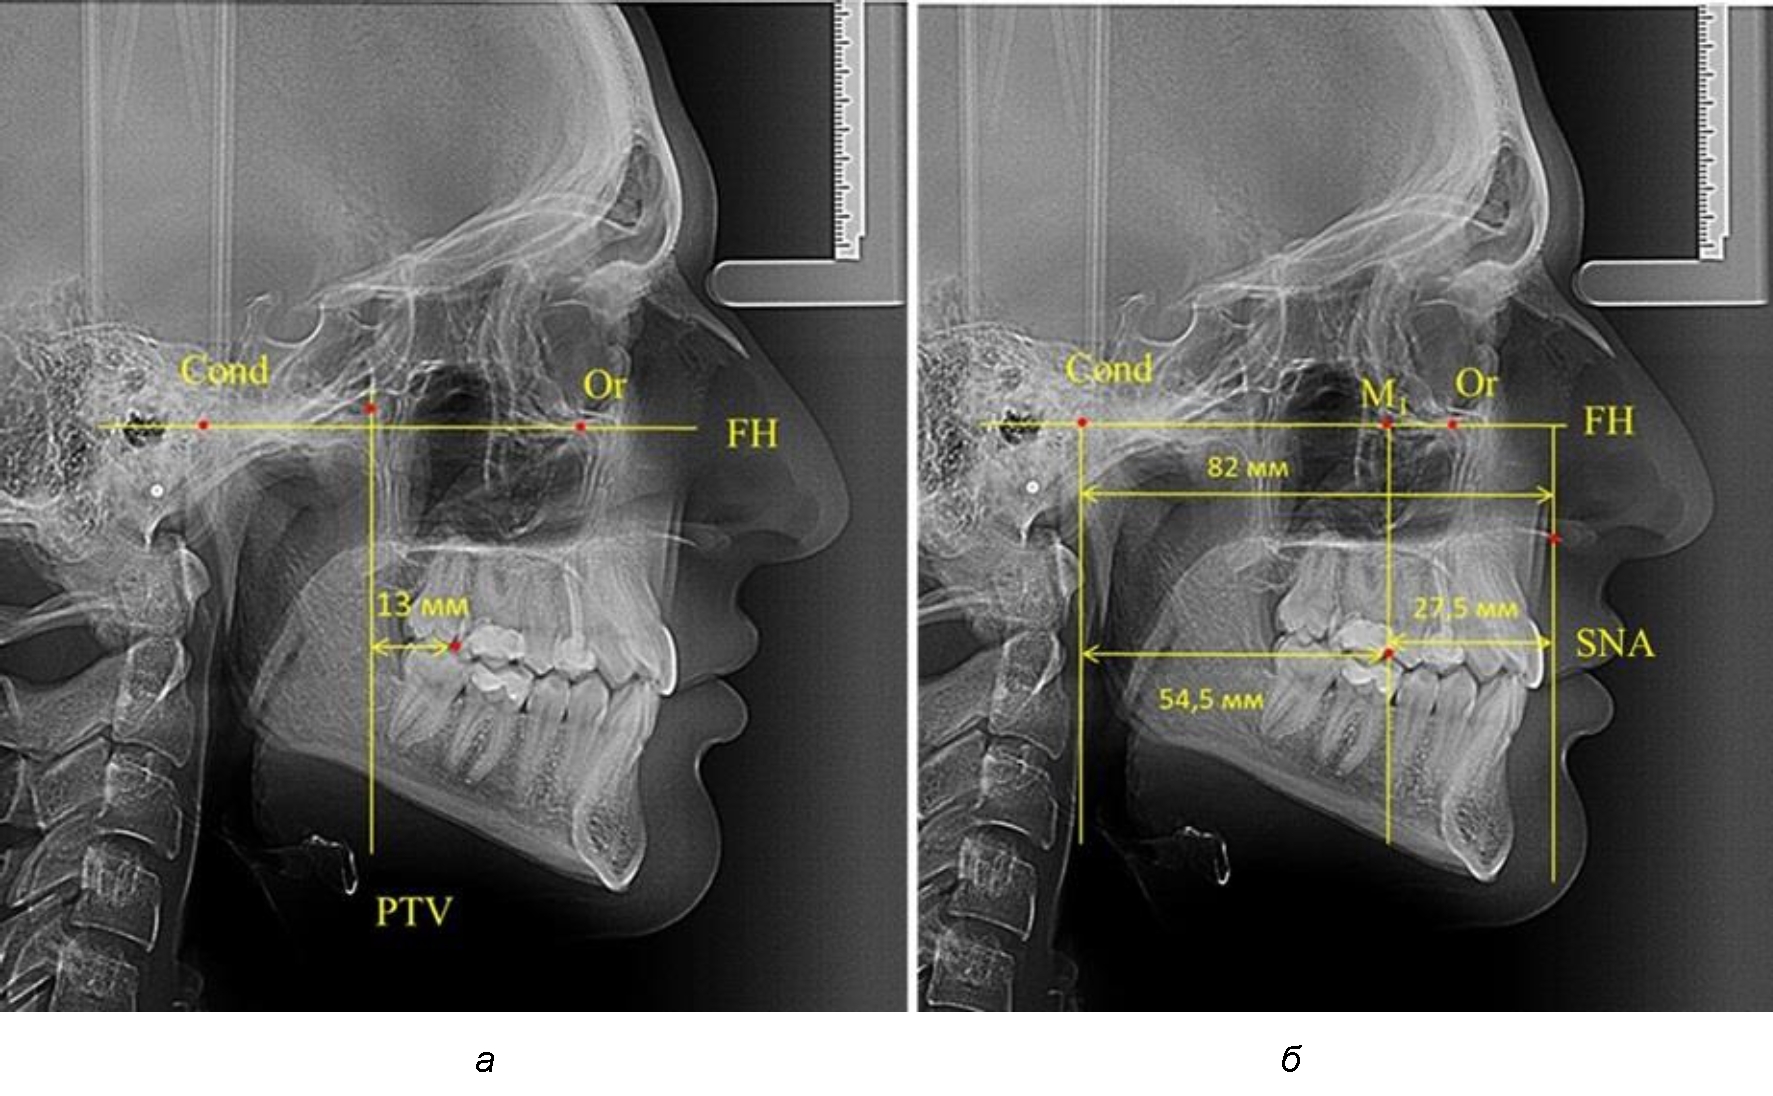

Рис. 1. Метод определения положения первых верхних моляров по Ralph E. McDonald (а) и по предложенному методу (б)

Так, при расстоянии от крыловидной вертикальной плоскости PTV до дистальной поверхности верхнего первого постоянного моляра в 13 мм сагиттальный размер гнатического отдела был 82 мм. При этом отношение кондилярно-спинального расстояния к кондилярно-молярному размеру (54,5) было близким к коэффициенту 1,5, что представлено на рис. 2.

Рис. 2. Особенности положения первых моляров по R. E. McDonald (а) и по предложенному методу (б) при уменьшенном молярно-крыловидном расстоянии